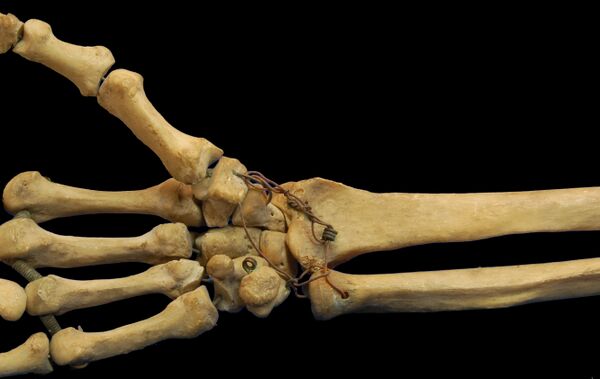

Суставные поверхности: суставная впадина образована лучевой костью и треугольным хрящевым диском, закреплённым между лучевой костью и шиловидным отростком локтевой кости, а суставная головка — проксимальной поверхностью первого ряда костей запястья (ладьевидной, полулунной и трёхгранной), связанных межкостными связками (лат. ligaméntum intercárpea)[1][2][3].